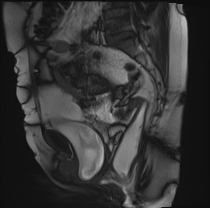

MRI

矢状位

静息动态扫描

研究显示,患者排便时盆底整体下降异常,肛提肌裂孔异常增宽。

可见肛直肠交界处严重异常下降。

可见直肠肛门内套叠,直肠折叠入肛管。另可见少量直肠前膨出。

可见中度膀胱膨出。

可见轻度阴道脱垂。

子宫未显影——子宫切除术后状态。